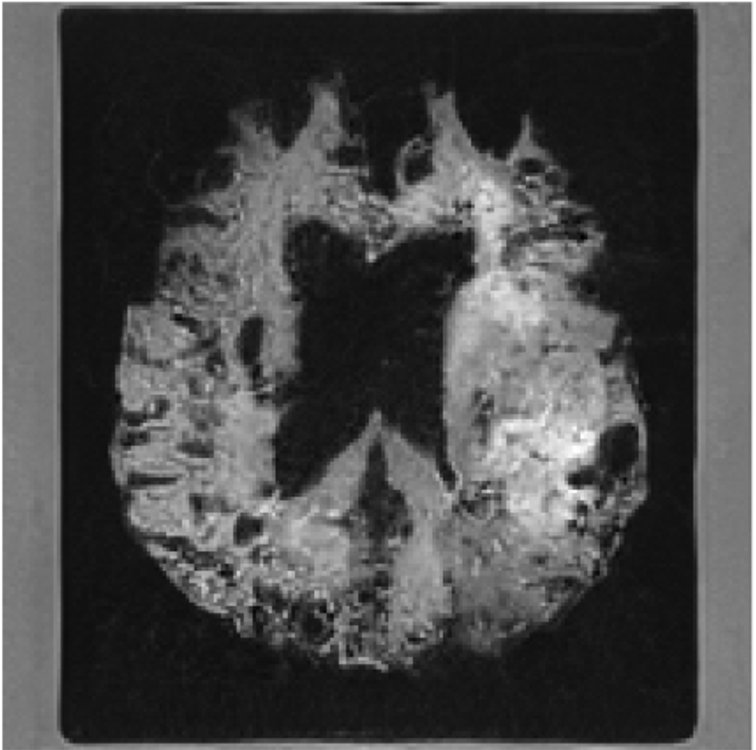

Refer to caption

(a) Ground-truth post-treatment MRI

(b) Reconstructed MRI from predicted post-treatment latent

Figure 6: Reconstruction comparison for post-treatment MRI.

Figure 7: Ground-truth versus predicted post–pre enhancement difference maps Δ(postpre)\Delta(\text{post}-\text{pre}). Both panels visualize directional intensity change, with red indicating increased enhancement and blue indicating decreased enhancement. The structural agreement shows that the model faithfully reconstructs treatment-sensitive Δ\Delta patterns.

8 Interpretability of Latent Prediction

To show the interpretability of framework, we additionally train a diffusion-based decoder that maps latent representations back into MRI space. This enables qualitative inspection of whether the predicted latent trajectory preserves meaningful anatomical and treatment-related changes.

Fig. 6 compares the ground-truth MRI with the diffusion-based reconstruction generated from the predicted latent state. The reconstructions remain structurally coherent, indicating that the latent space retains sufficient information for image-level interpretation. Fig. 7 further contrasts the pre-treatment MRI with the post-treatment reconstruction derived from the predicted latent state. Observable structural differences align with expected treatment effects, suggesting that the model captures clinically plausible disease evolution patterns.

These qualitative results demonstrate that our latent predictions encode meaningful morphological changes that support interpretability of the model’s dynamics.